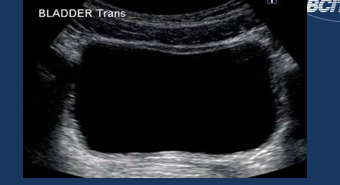

What does anechoic mean (EXAM)?

-black

-fluid filled (blood urine, serous cyst)